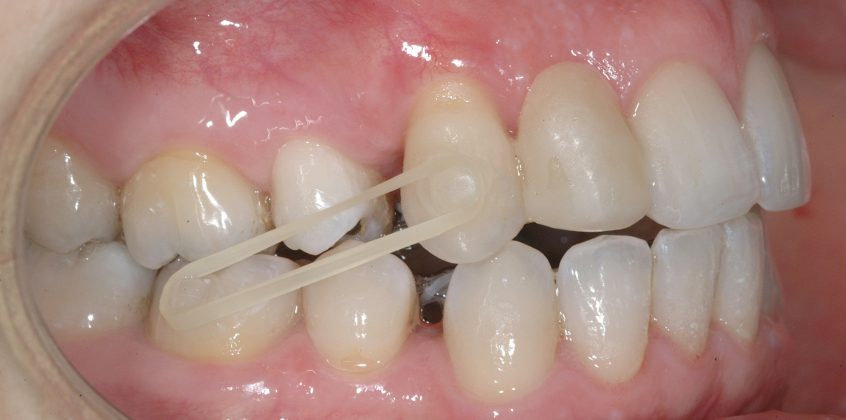

Il protocollo terapeutico ha previsto l’estrazione del primo premolare inferiore sinistro (3.4) e del primo superiore destro (1.4), l’applicazione di una apparecchiatura fissa linguale 2D e di una meccanica asimmetrica di ancoraggio e movimento ortodontico a entrambe le arcate (Figure 3a-b).

Il trattamento è iniziato con l’estrazione dei due premolari in unica seduta in anestesia locale e l’applicazione simultanea, dopo una settimana, della apparecchiatura linguale inferiore e superiore, non essendoci problemi di overbite e potenziali interferenze in occlusione tra l’apparecchiatura superiore e i frontali inferiori. All’arcata superiore è stata effettuata una iniziale chiusura dello spazio estrattivo con forze molto leggere in ancoraggio medio su arco .014” Nichel-Titanio e successivamente .016” Nichel-Titanio, bondato in prima fase per maggior stabilità direttamente sulla superficie mesiale di 2.4.

Nota tecnica: il movimento iniziale di distalizzazione della corona di 1.3 mediante tipping distale (vista la posizione radicolare iniziale) è stato ottenuto con una catenella elastica leggera inserita su 1.6, 1.5 e ancorata su 1.3, abbracciando per maggior controllo l’aletta disto-occlusale e quella gengivale del bracket linguale.